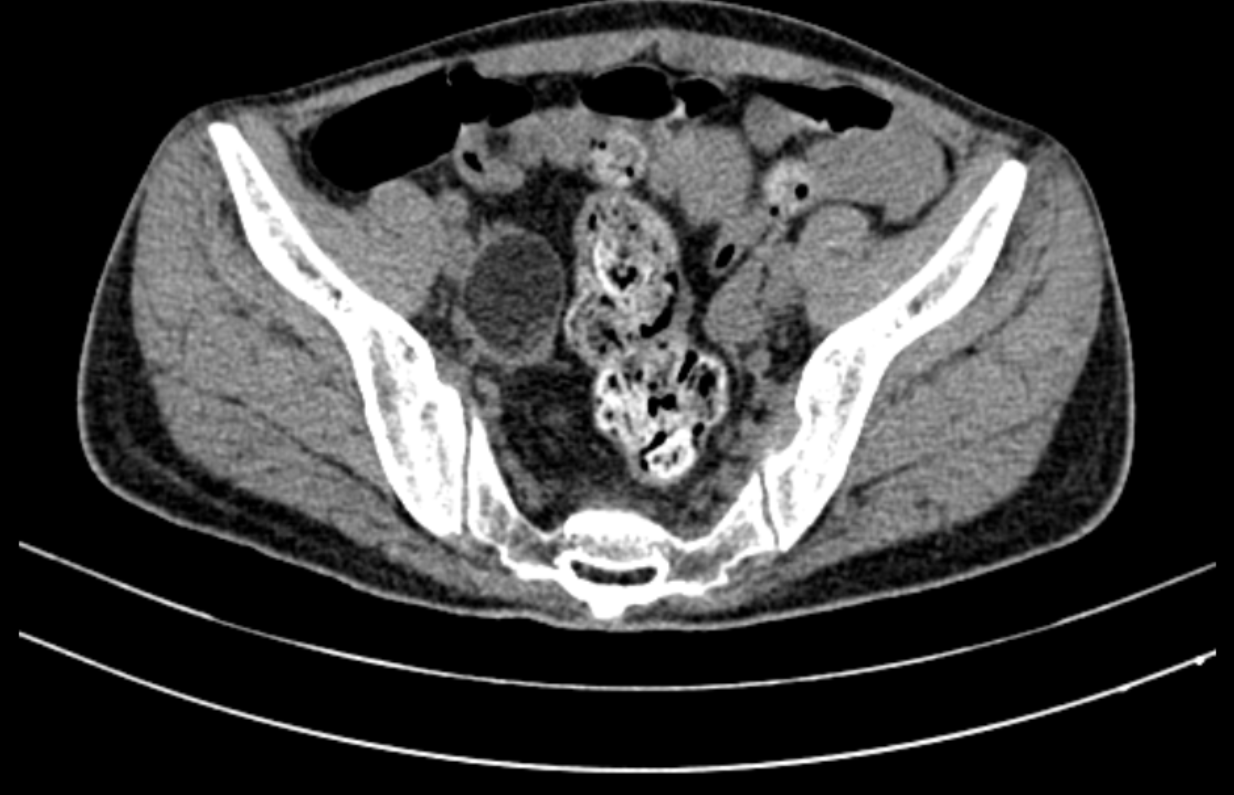

| Hình ảnh khối u quái buồng trứng bên phải - nguyên nhân gây bệnh lý viêm não tự miễn cho bệnh nhân (ảnh: BVCC) |

Qua chẩn đoán hình ảnh, các bác sĩ phát hiện bệnh nhân bị khối u ở buồng trứng. Kết quả sinh thiết tế bào dưới kính hiển vi cho thấy đây là dạng u quái - nguyên nhân gây bệnh viêm não tự miễn kháng thể kháng thụ thể NMDA ở phụ nữ. Sau 7 lần thay huyết tương, người bệnh được phẫu thuật nội soi cắt u quái thành công. Gần 1 tháng sau cuộc mổ, sức khỏe của người bệnh đã bình phục tốt, đủ điều kiện xuất viện.